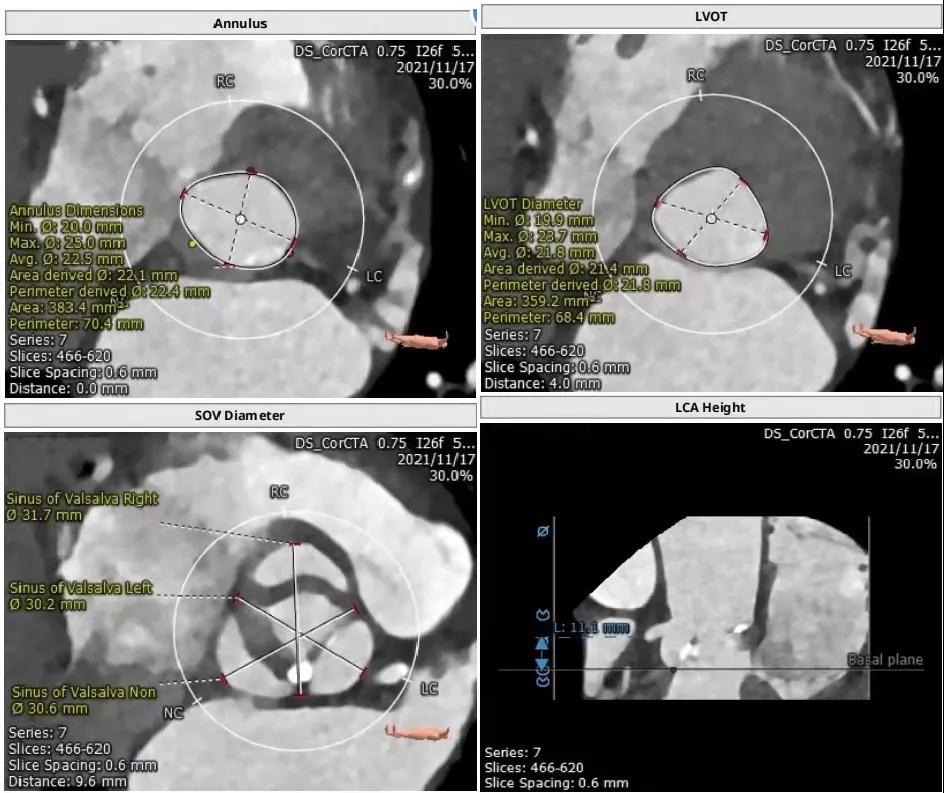

主动脉瓣CT评估:

三叶瓣,瓣环直径22.4mm,瓣环长短径分别为25.0*20.0mm,周长为70.4mm,面积为383.4mm²。左室流出道直径21.8mm,瓦式窦31.7mm*30.2mm*30.6mm,左冠高度11.1mm,右冠高度15.3mm,窦管交界直径26.3mm。

根部解剖: